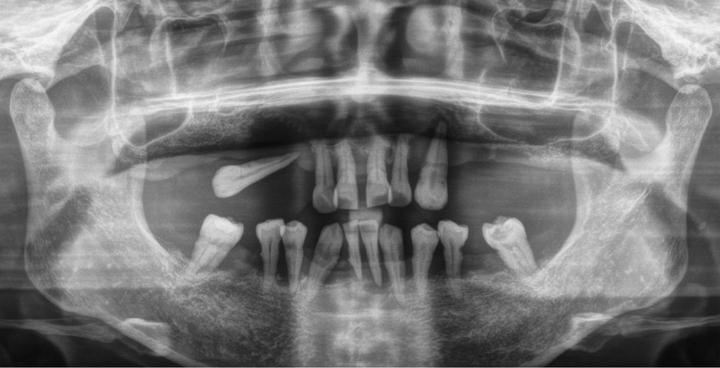

-拍牙片

了解缺牙的位置情况以及牙槽骨情况